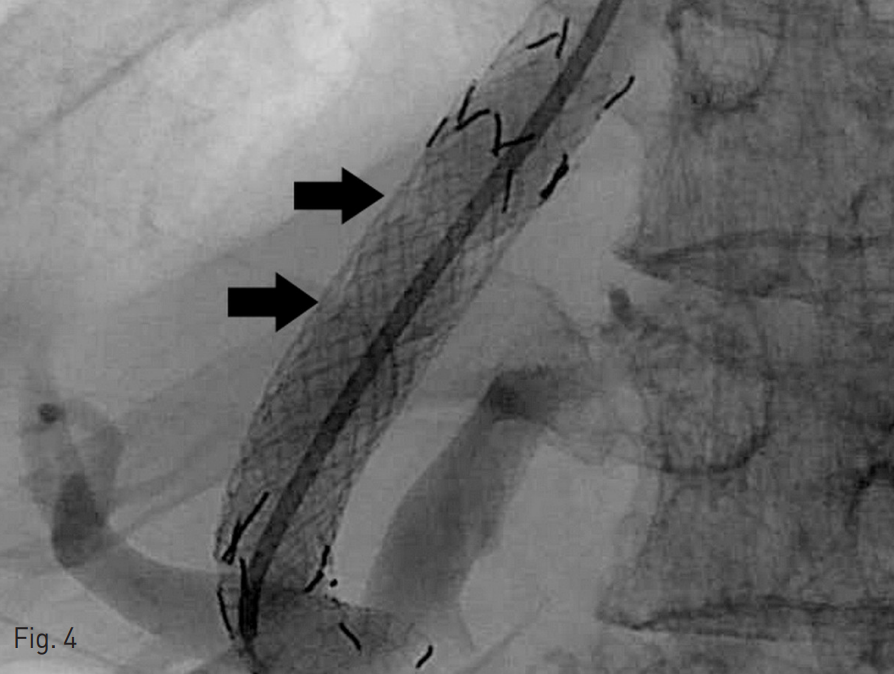

Fig. 4

After second revision, double point tied (arrows) constrained stent is positioned at TIPS tract.

시술 이후에도 3등급의 간성혼수 증상이 지속되어 2주 뒤 다시 두 번째 revision을 계획하였다. 시술 전 문맥-간정맥 압력 차는 11 mmHg였다. 10 mm x 6 cm 풍선 카테터 (Mustang, Boston Scientific, Natick, MA, USA)를 이용하여 첫 번째 revision때 삽입하였던 stent의 6mm로 좁혔던 부분을 펴준 뒤 (Fig. 3) 두 군데를 5 mm로 묶어서 만든 10 mm stent graft를 내부에 재설치하였다 (Fig. 4). 시술 이후 문맥간정맥압 차이는 16 mmHg로 측정되었다. 이후 환자의 간성혼수 증상이 grade 2로 호전되었다.